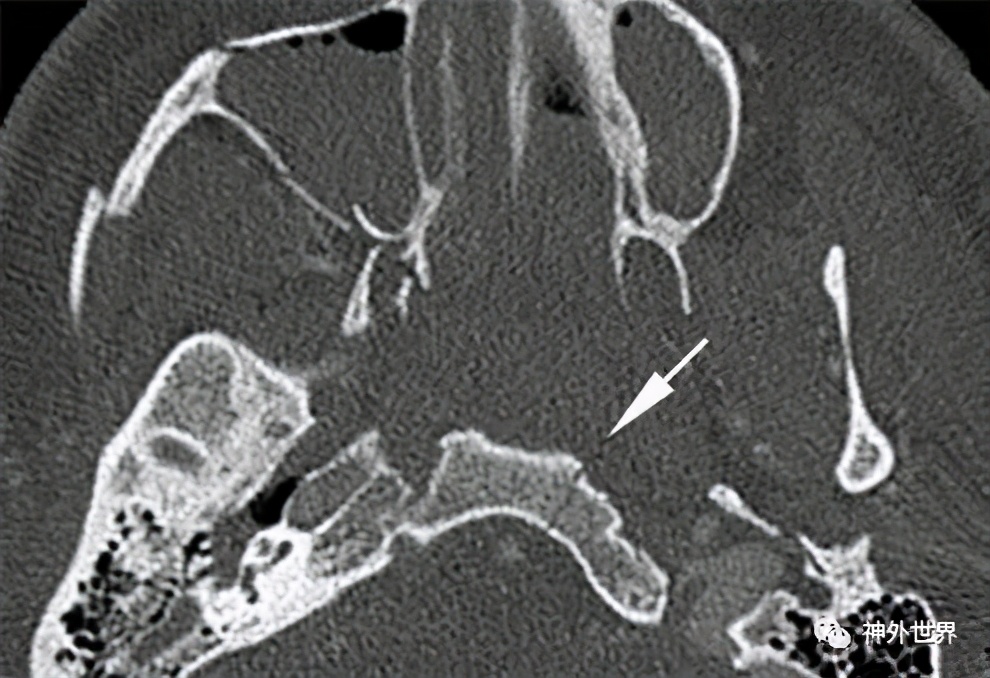

图11:斜坡骨折 。CT示斜坡非移位性斜行骨折(箭头)。合并右翼突 内测 板、右颧弓和右上颌窦壁骨折